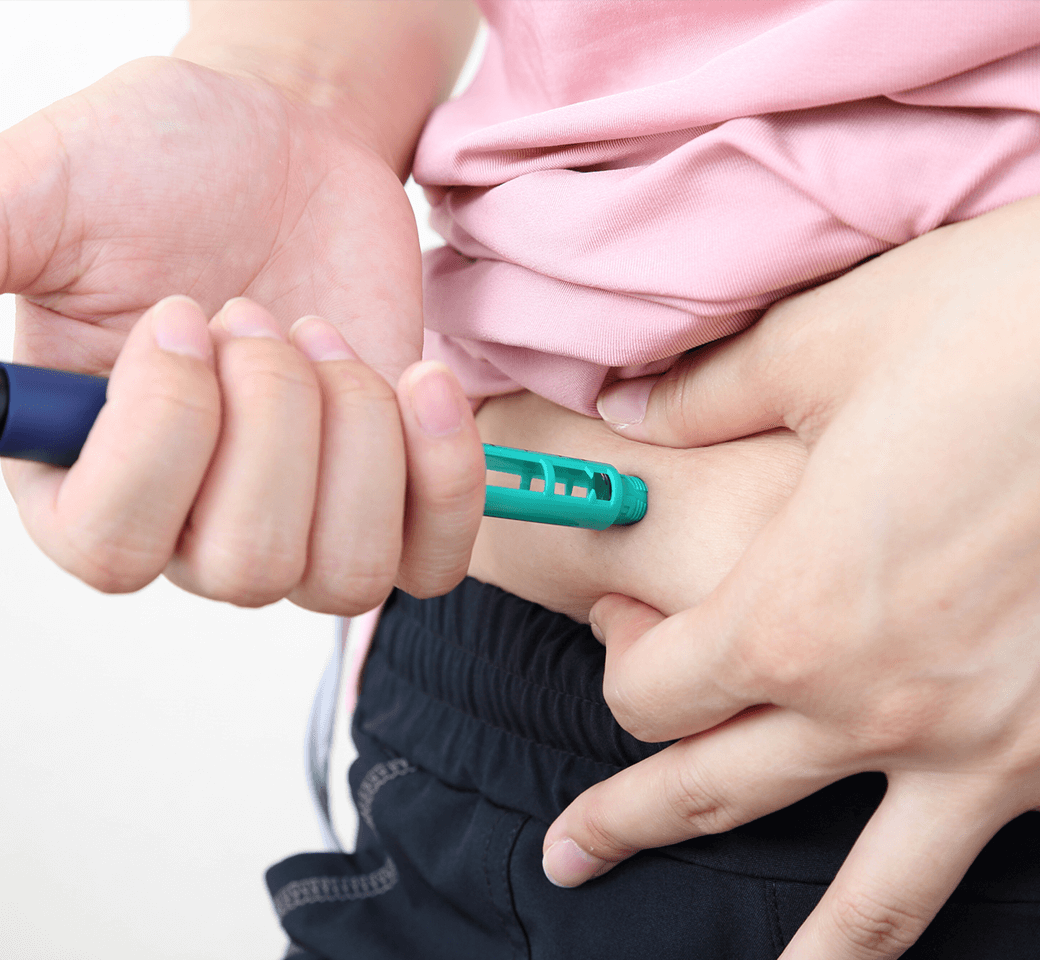

成長ホルモン療法は、通常、毎日または週1回の自己注射によって行います。

使用する注射器はペン型が主流で、針は非常に細く、皮下に浅く注射するため痛みは最小限です。多くの方が数回で慣れ、日常生活に大きな負担なく継続できます。

当院では、初回時に専門スタッフが実演を交えた丁寧な指導を行い、患者さまやご家族が安心して自宅で行えるようサポートします。また、注射のタイミングや部位のローテーション、保管方法なども分かりやすくご案内し、必要に応じてフォローアップも実施しています。

治療を長期的に安全かつ効果的に続けるため、「痛みの少なさ」「操作の簡便さ」「継続しやすい環境」を重視しています。 -